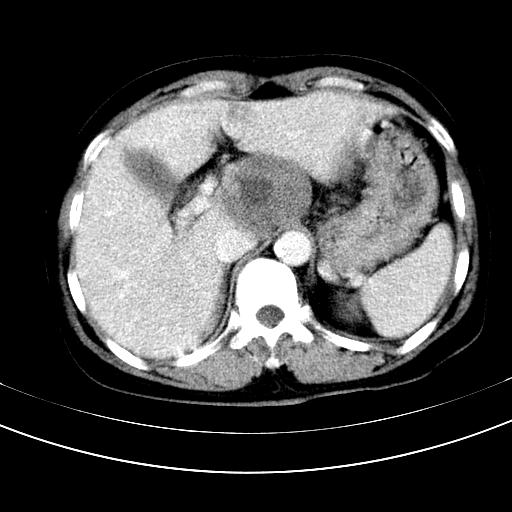

补充强化片

肝左叶及尾叶低密度灶,增强有渐进性明显强化,考虑血管瘤。胃内“充缺”首先要排除异物(食物),变换体位可鉴别。增强时机抓的不好,还应该有延时像。

谢谢楼主的增强片子,平扫没发现左侧肾上腺的问题很不好意思,可惜片子只有门脉期,所以还只有猜,肝脏的病灶在门脉期部分强化,首先考虑为血管瘤(其他的用一种病不好解释)胃要喝水就好了现在不好说是否有问题,左肾上腺的问题考虑是肿瘤。

做了增强后,可以明确胃是没有肿瘤的,肾上腺也没有肿瘤.肝左叶的病灶首先考虑血管瘤,应该再延迟,肝尾状叶的病灶仍不能排除肝癌的可能性.